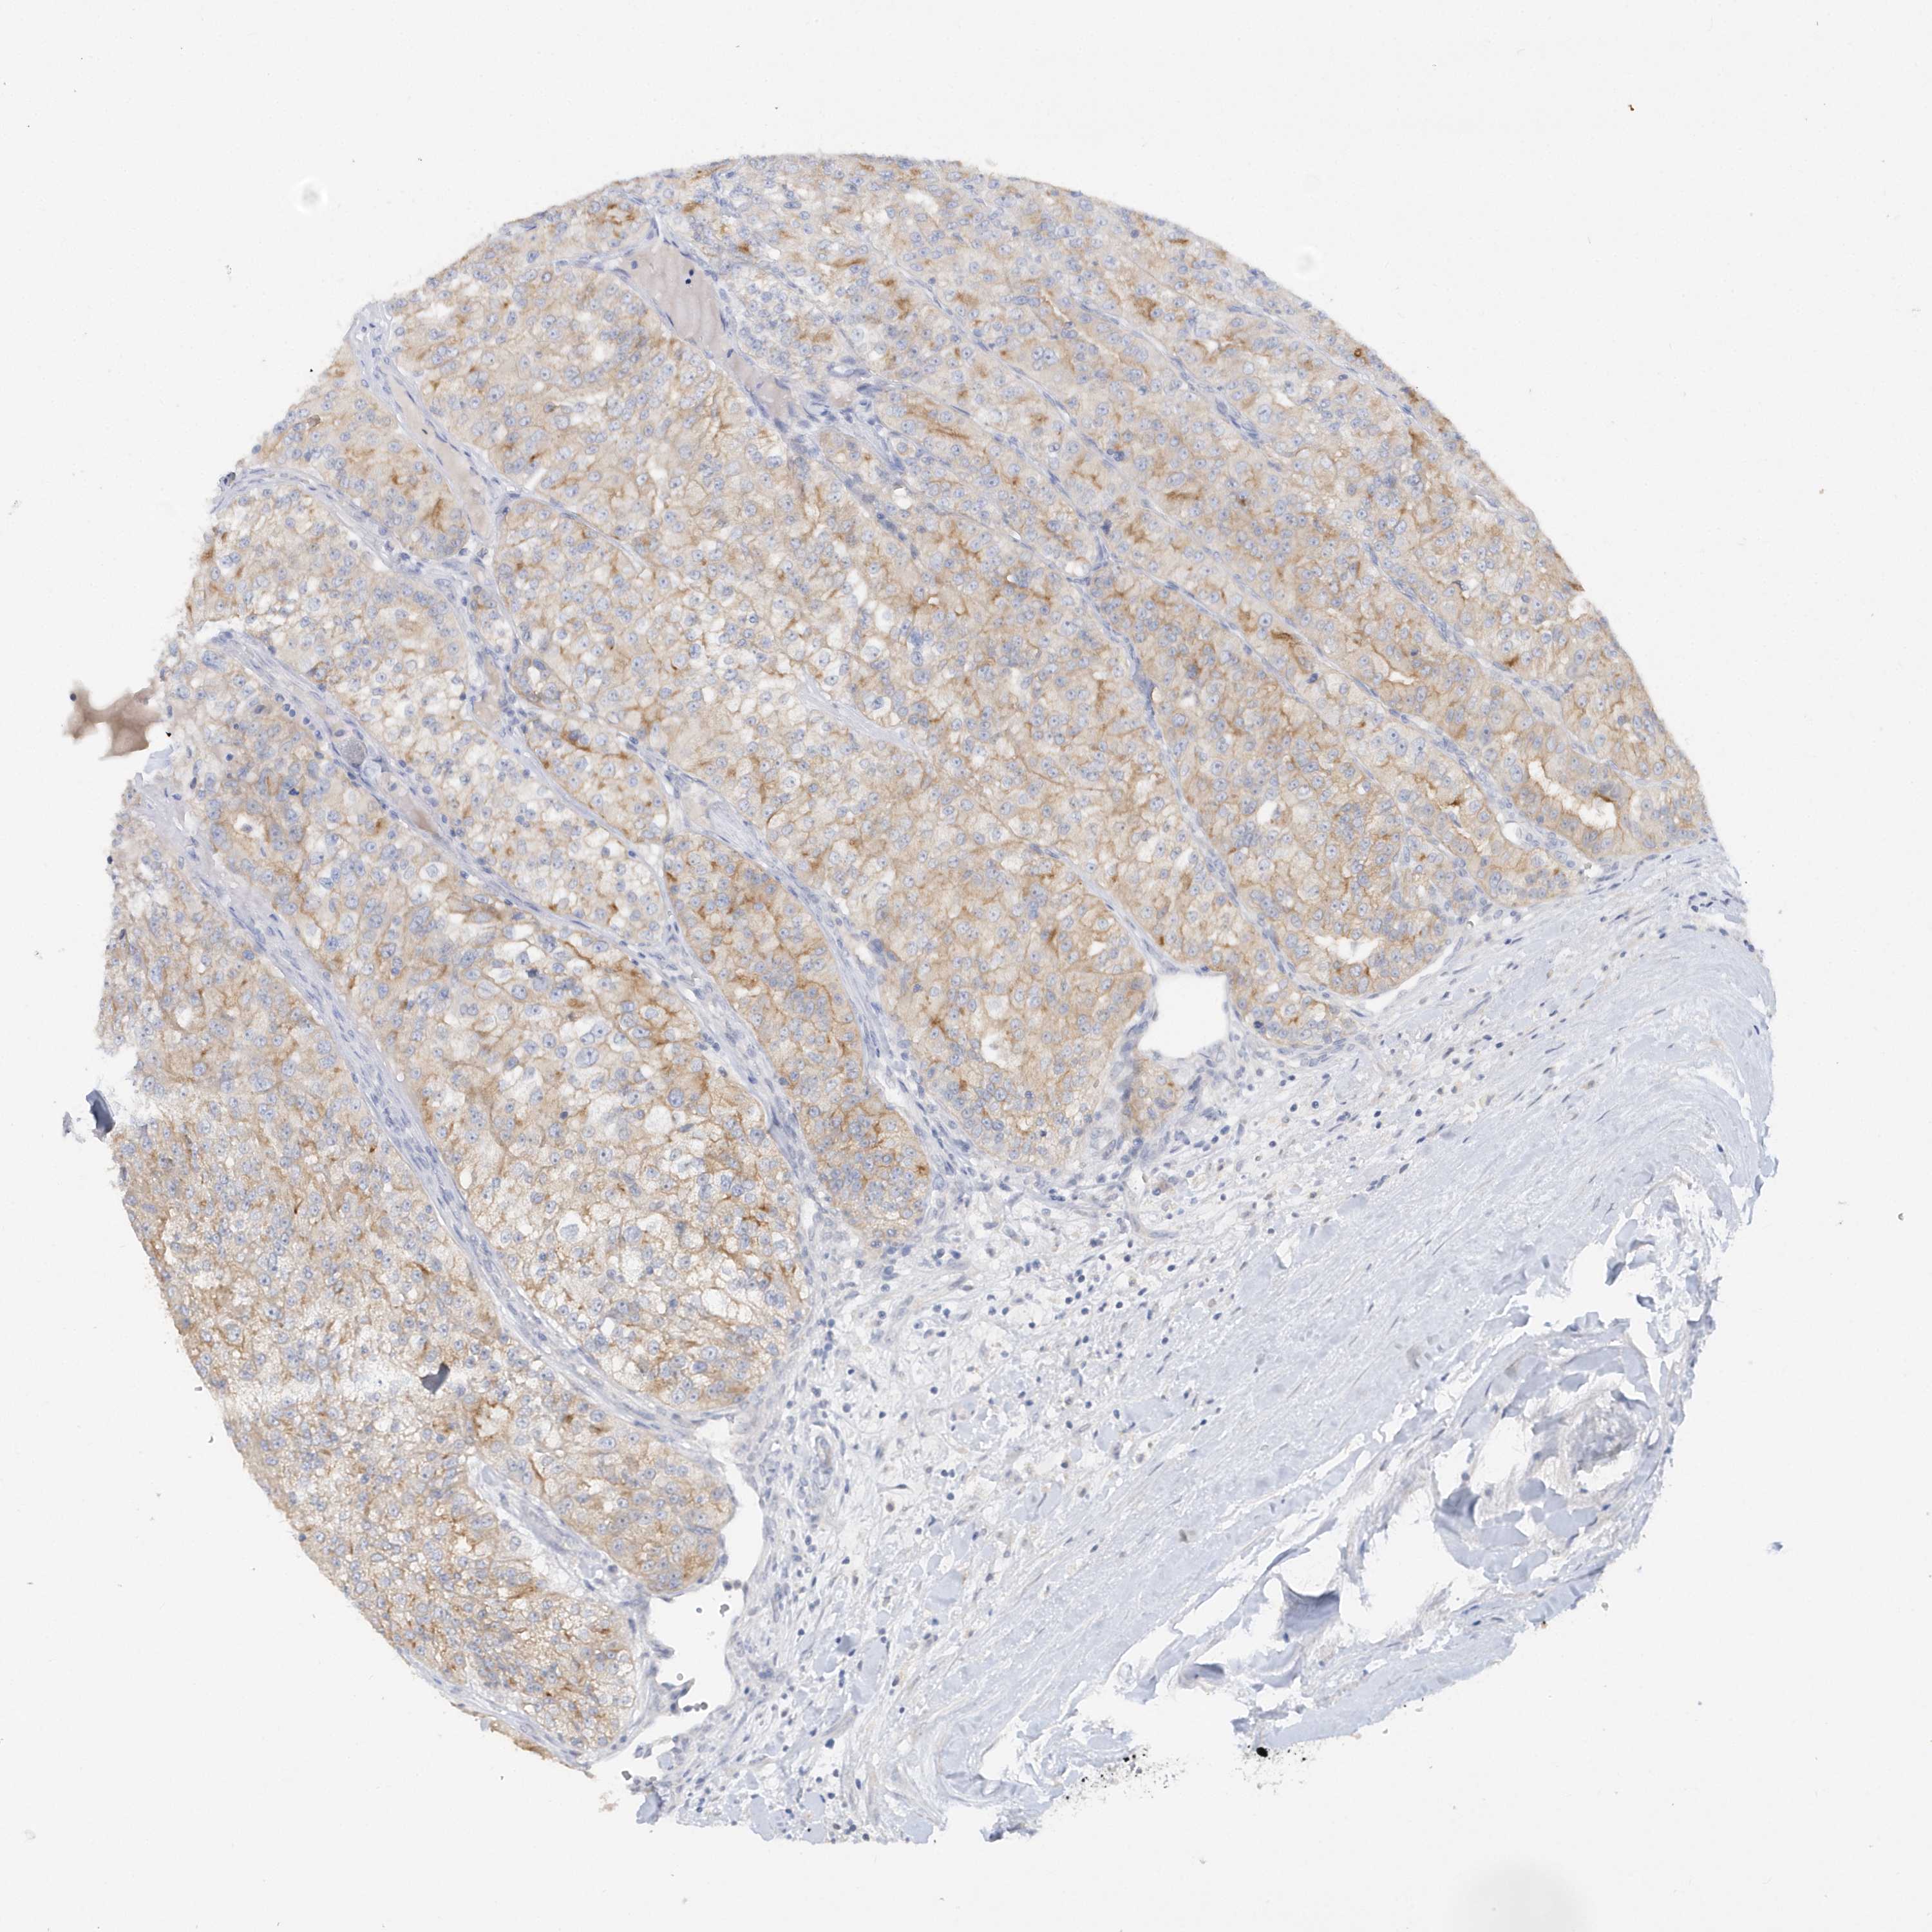

RPE is not prognostic in Kidney Renal Clear Cell Carcinoma (validation)

: 38.64

Average pTPM 35.9

Number of samples 100